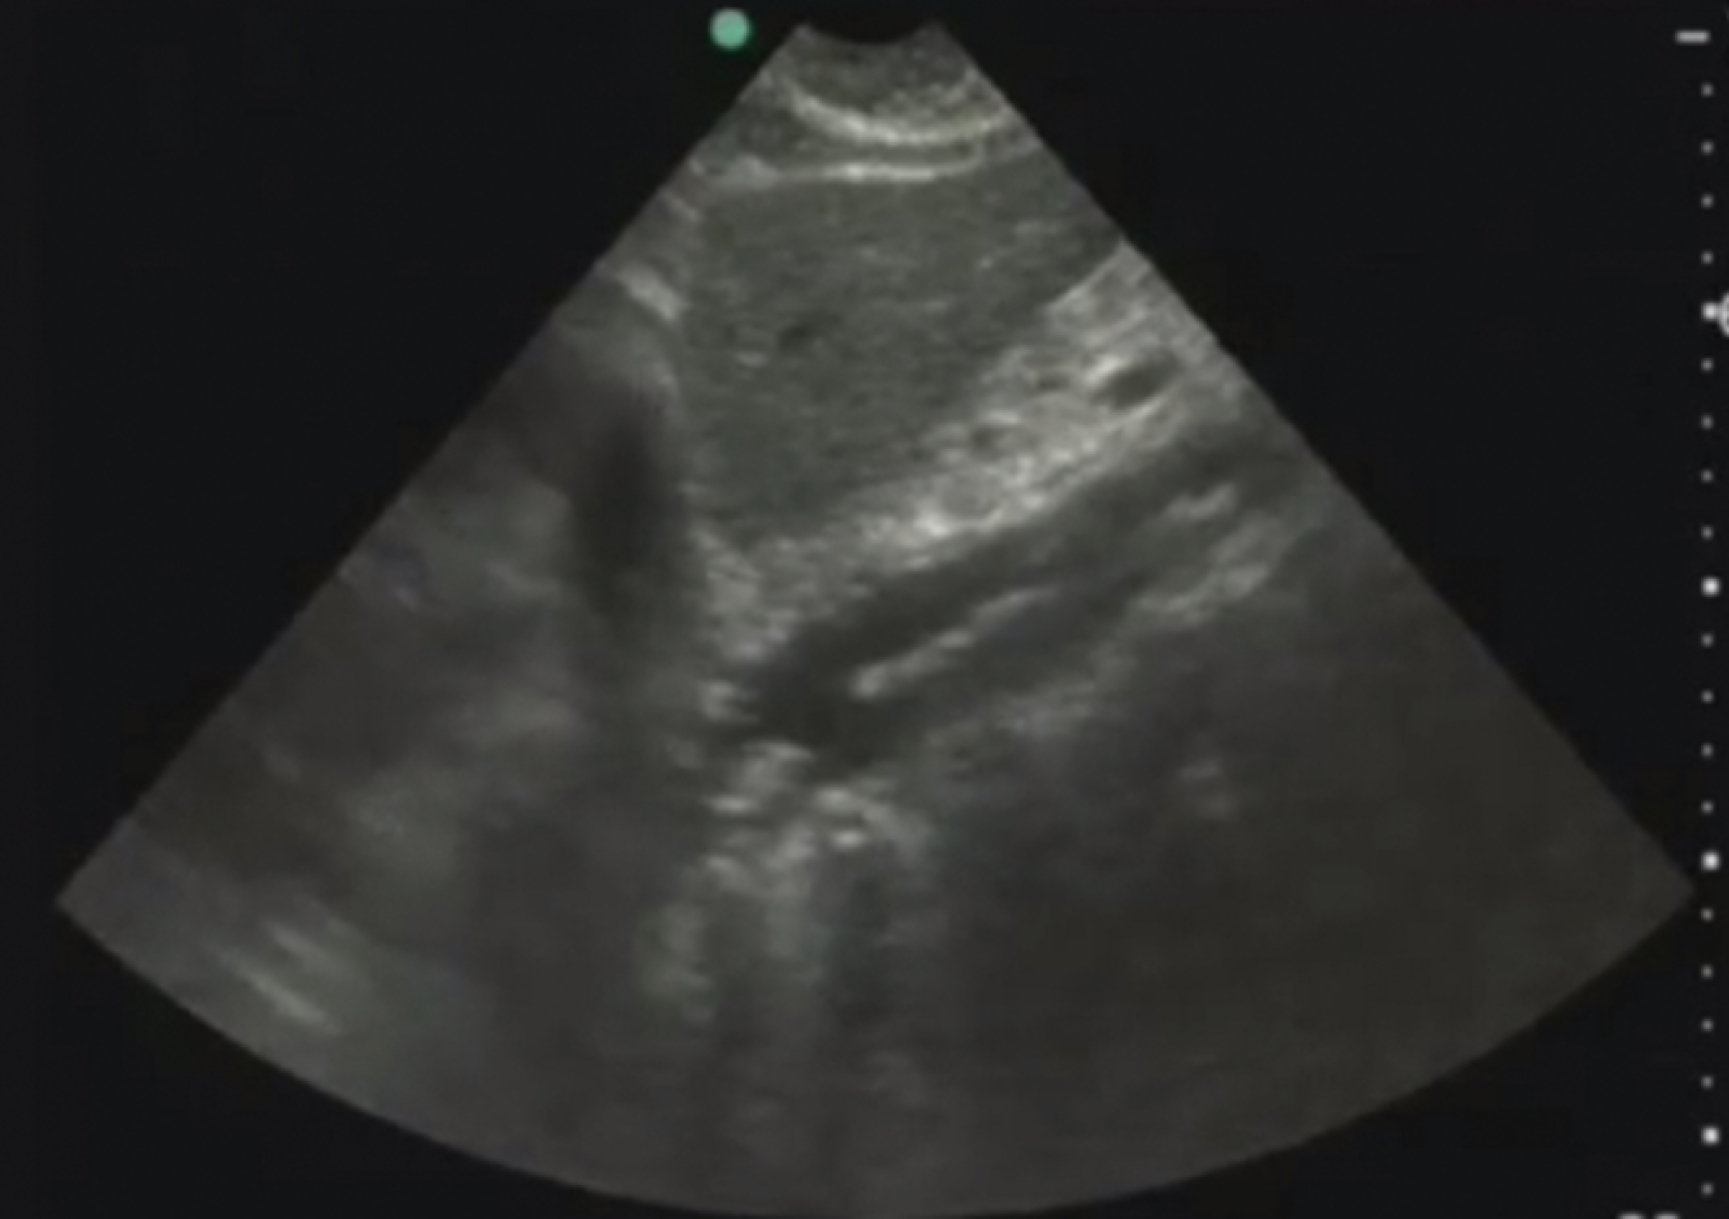

Image Acquisition

Using a low-frequency transducer (curvilinear or phased array) and significant pressure to displace the overlying bowel gas, the aorta should be visualized from the subxiphoid region to the umbilicus (bifurcation) in both transverse and longitudinal planes. The transverse view should be obtained first to avoid the cylinder tangent error, which could falsely underestimate the size of the aorta ( Fig. e3.7 and Video e3.6 ). Cross-sectional measurements should be taken of the aorta, outer wall to outer wall, including any mural thrombus that might be present. Aortic dissection may be detected by a combination of abdominal and cardiac scanning, with the addition of a suprasternal notch view to the traditional cardiac windows.

Normal transverse view of the aorta.